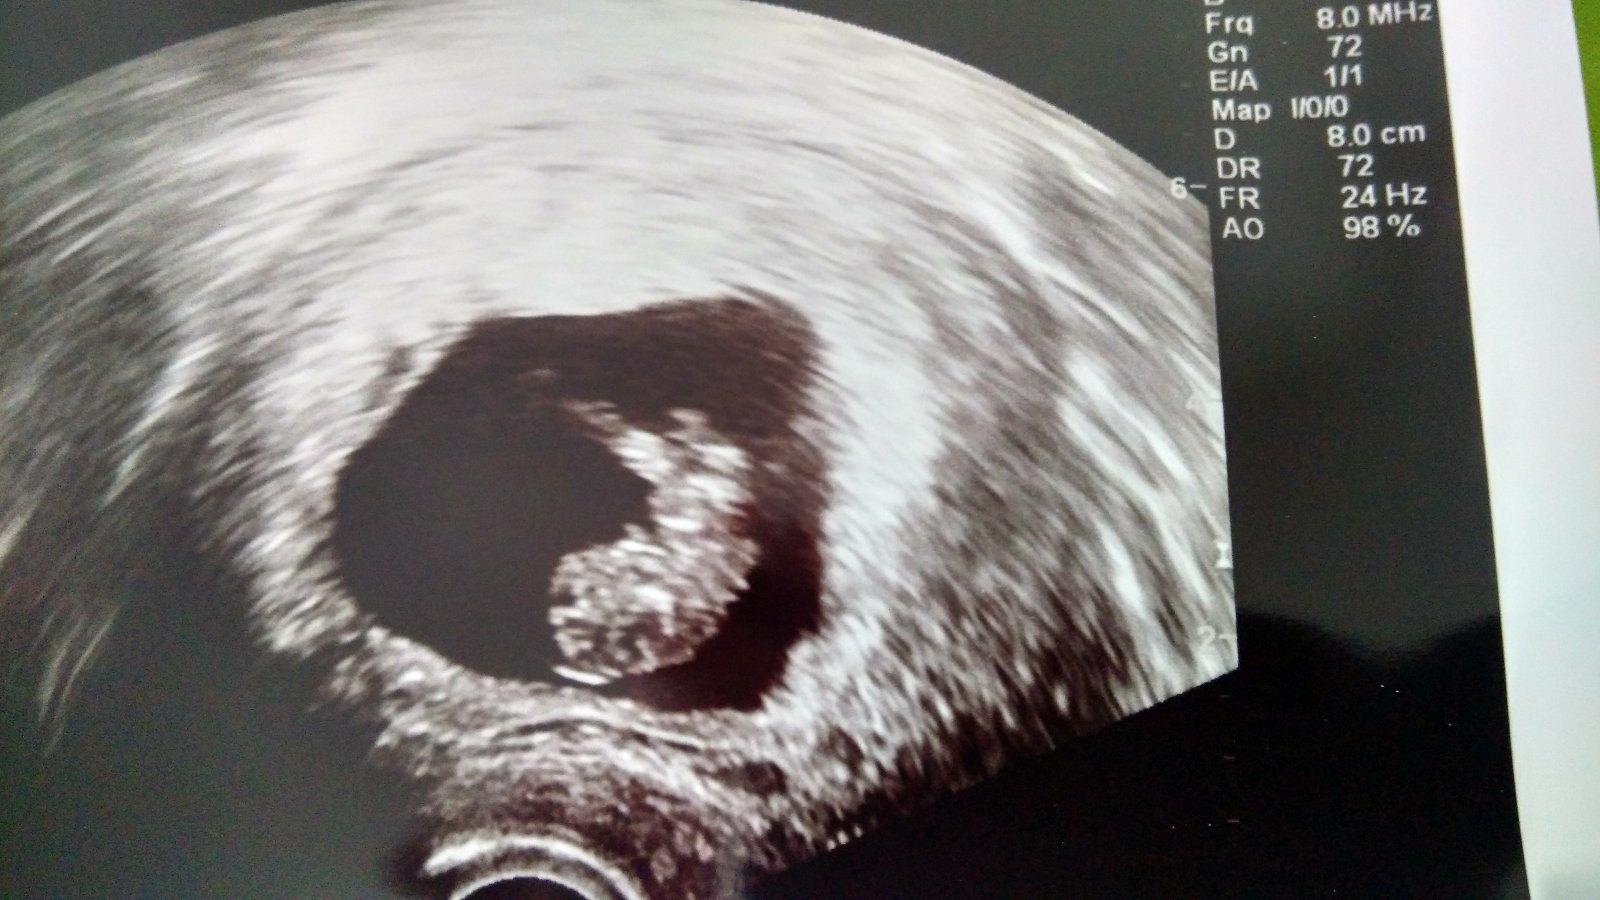

Babulky , nevzdavajte sa ak sa nenahnevate chcem vas potesit a poslat pozitivnu energiu ..ked som bola pred iui som si citala pozitivne odpovede od vas a nakoplo ma to a verila som ze sa nam to podari..vcera som bola na sone sme v 9tt a drobceka bolo krasne vidno dokonca hybalo rucickami ...drziim vam palce